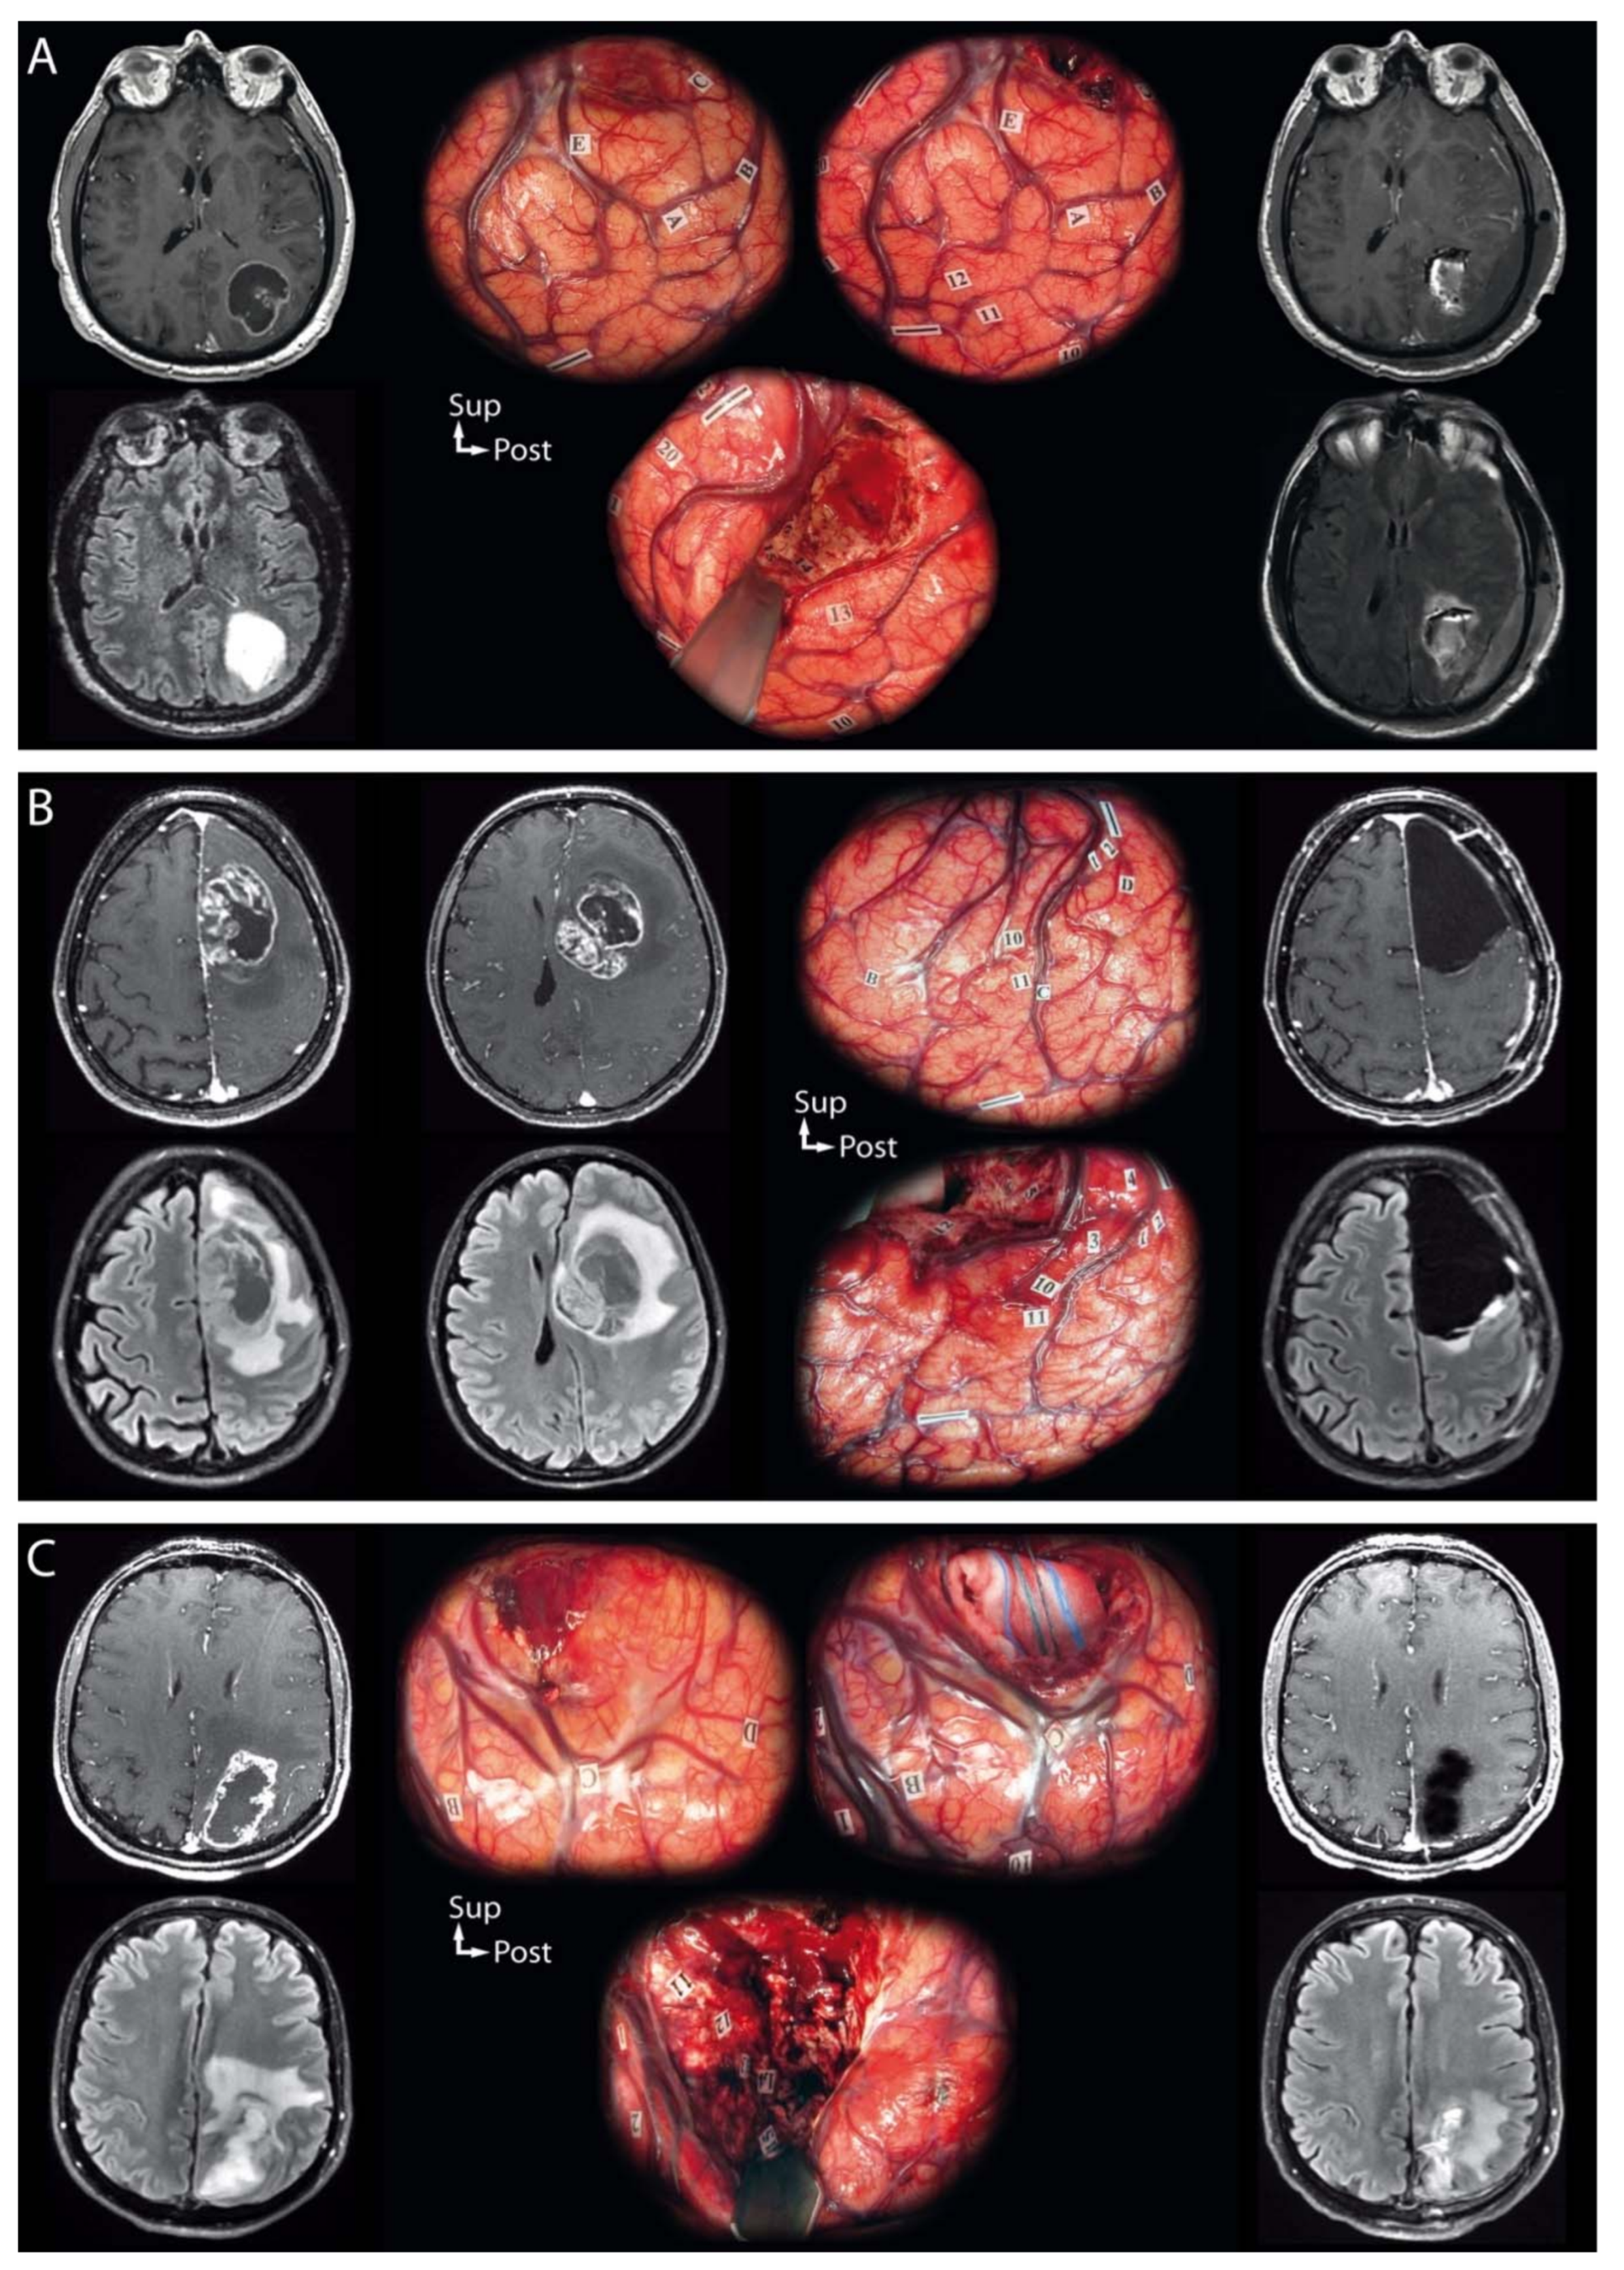

Figure 2.

Illustrative cases of the intraoperative management of tumor-related elevated intracranial pressure and local mass effect during awake resection using intraoperative direct cortico-subcortical electrostimulation mapping of IDH-wildtype glioblastomas. On the left, preoperative magnetic resonance examinations (post-contrast T1-weighted and Fluid Attenuated Inversion Recovery sequences); in the middle, intraoperative photographs with eloquent sites tagged; on the right, day-one postoperative magnetic resonance examinations (post-contrast T1-weighted and Fluid Attenuated Inversion Recovery sequences). (A) A 63-year-old right-handed man presented with uncontrolled focal seizures revealing a left cystic contrast-enhancing necrotic parietal tumor. An awake resection was performed using intraoperative direct cortico-subcortical electrostimulation mapping. The initial cortical mapping (up to 6.0 mA) failed at identifying any eloquent sites. Intralesional debulking was performed, which reduced mass effect. Subsequent cortical mapping allowed for the identification of the primary motor cortex of the face (1) and hand (2), and of latency and semantic paraphasia in the supramarginal gyrus (10, 11, 12, 13). Then, the resection was performed beyond the limits of the solid tumor tissue component according to subcortical functional boundaries, with the arcuate fasciculus as the lateral limit of the surgical cavity (latency, 14, 15, 16). No visual disturbances were observed at the inferior limits of the surgical cavity. (B) A 39-year-old right-handed woman presented with signs of elevated intracranial pressure and language impairment revealing a left cystic contrast-enhancing necrotic frontal tumor. An awake resection was performed using intraoperative direct cortico-subcortical electrostimulation mapping. The initial cortical mapping (3.5 mA) allowed for the identification of the ventral premotor cortex inducing speech arrest (10, 11) and of the primary motor cortex of the hand (1, 2) with no other response elicited on cortical mapping. An ultrasound-guided cyst puncture was performed to reduce mass effect, which revealed the cortical negative motor networks inducing arrest of voluntary movements of the hand (3, 4) upon electrostimulation. Then, the resection was performed beyond the limits of the solid tumor tissue component according to subcortical functional boundaries, with the white matter involved in motor control as the posterior limit of the surgical cavity (arrest of voluntary movements, 5, 6, 7) and the arcuate fasciculus as the lateral limit of the surgical cavity (phonemic paraphasia, 12). (C) A 43-year-old right-handed man presented with focal seizures revealing a left contrast-enhancing and necrotic parietal tumor. An awake resection was performed using intraoperative direct cortico-subcortical electrostimulation mapping. Upon opening the dura, brain herniation occurred, and the patient experienced headaches, leading to initial cortical mapping failure. Intralesional debulking was performed, which reduced the mass effect and headaches. Subsequent cortical mapping (4.0 mA) allowed for the identification of the primary sensory cortex of the hand (1) and upper limb (4) and of semantic paraphasia in the supramarginal gyrus (10). Then, the resection was performed beyond the limits of the solid tumor tissue component according to subcortical functional boundaries, with the white matter involved in sensory control as the anterior limit of the surgical cavity (11, 12, 13, 14 for the lower limb; 15 for the upper limb). No visual or language disturbances were observed at the lateral and inferior limits of the surgical cavity.